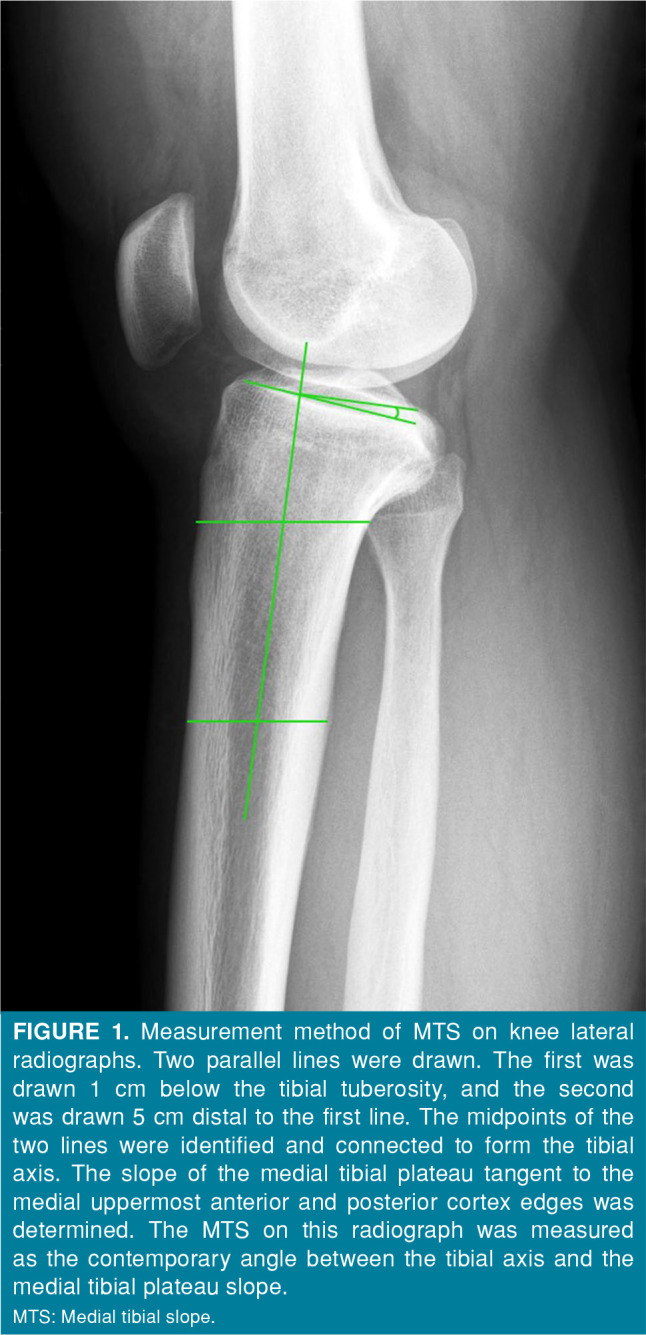

Patients and methods: This retrospective study included 97 patients (93 males, 4 females; mean age: 30.8±8.3 years; range, 17 to 49 years) with anterior cruciate ligament (ACL) injuries who subsequently underwent double-bundle ACL reconstruction by a single surgeon between January 2005 and December 2014. The MTS was measured on lateral knee radiographs, and MTS and LTS were measured on MRIs. Three different reviewers, including a postgraduate year doctor, an orthopedic resident, and an attending orthopedic surgeon, performed the measurements. Each reviewer measured the slope of the same image three times. The correlations of MTS on radiographs and MTS/LTS on MRIs were calculated. Intra- and interobserver reliability were evaluated.